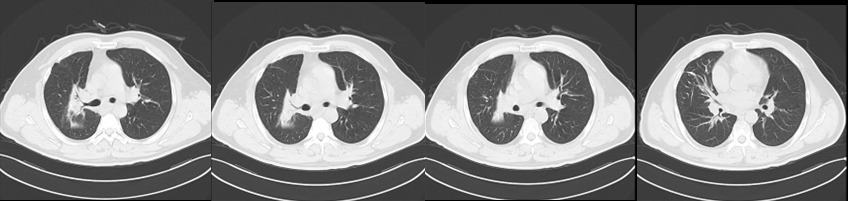

治疗前

治疗后

两年过去了。最近一次复查胸部CT显示:原发病灶显著缩小,转移淋巴结持续消退。王先生恢复了正常生活,能走能跑,不再喘憋。